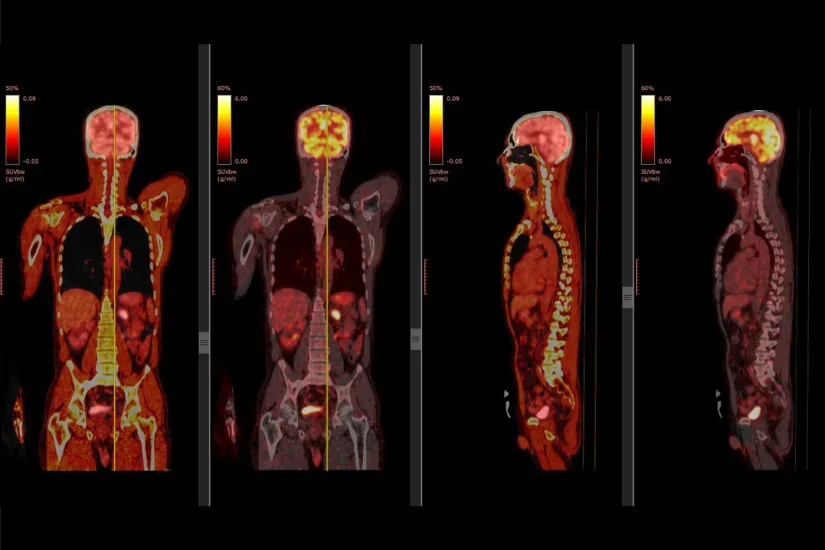

PET poate detecta activitatea metabolica atipica inainte ca boala sa poata fi identificata cu ajutorul altor teste imagistice, cum ar fi tomografia computerizata (CT) sau imagistica prin rezonanta magnetica (IRM). Mai mult, prin incorporarea in echipamentul PET a unui computer tomograf (CT) se obtine un echipament hibrid PET-CT, care permite printr-o singura examinare localizarea cu precizie a leziunilor active metabolic identificate.

Marea majoritate a investigatiilor PET/CT se efectueaza pentru patologia oncologica, deoarece celulele canceroase, fiind foarte active, vor consuma mai multa glucoza si astfel vor capta mai mult radiotrasor. Investigatia PET/CT permite o mai buna stadializare prin depistarea precoce a metastazelor, urmarirea raspunsului la tratament si, in general, imbunatatirea managementului pacientilor cu cancer.

Scanner-ul PET este dotat cu un tip specific de detector si un sistem computerizat care permite vizualizarea si localizarea spatiala a leziunilor intens metabolice. Rezolutia acestor echipamente este foarte inalta, cu atat mai inalta cu cat nivelul de fixare a radiofarmaceuticului este mai mare.

Prin incorporarea in echipamentul PET a unui computer tomograf (CT) se obtine un echipament hibrid PET-CT. Acesta prezinta avantajul obtinerii printr-o singura examinare a unei imagini care permite localizarea cu precizie a leziunilor active metabolic identificate. In imaginea de mai sus, in stanga este examinarea PET, in timp ce imaginea centrala este o scanare CT, iar imaginea din dreapta este obtinuta prin suprapunerea celor doua imagini.

Principalul determinant al folosirii PET/CT la pacientii cu tumori maligne este reprezentat de caracteristicile biologice ale celulei neoplazice. Celulele canceroase sunt foarte active si au nevoie de mai multa energie decat celulele normale. Drept urmare, folosesc mai multa glucoza. Fluorodeoxiglucoza (FDG) este un compus similar cu glucoza. Celula maligna va consuma glucoza radiomarcata in cantitate mare, iar energia emisa va fi detectata de dispozitivul PET cu obtinerea de imagini care evidentiaza locatia radiotrasorului in corp. Celulele canceroase apar ca pete luminoase pe scanarile PET.